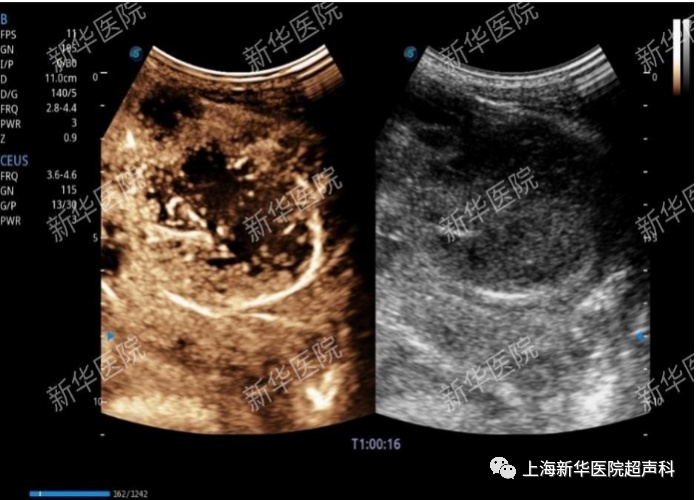

(5)超声造影实时引导和超声造影-MRI/CT影像融合导航:超声造影实时引导有助于确保活检获得活性组织,避免穿刺坏死组织;超声造影与CT/MRI融合导航下实时引导,有助于定位及诊断肝内隐匿性微小病灶,扩大了穿刺及消融治疗的适用人群及范围。

肝肿瘤超声造影